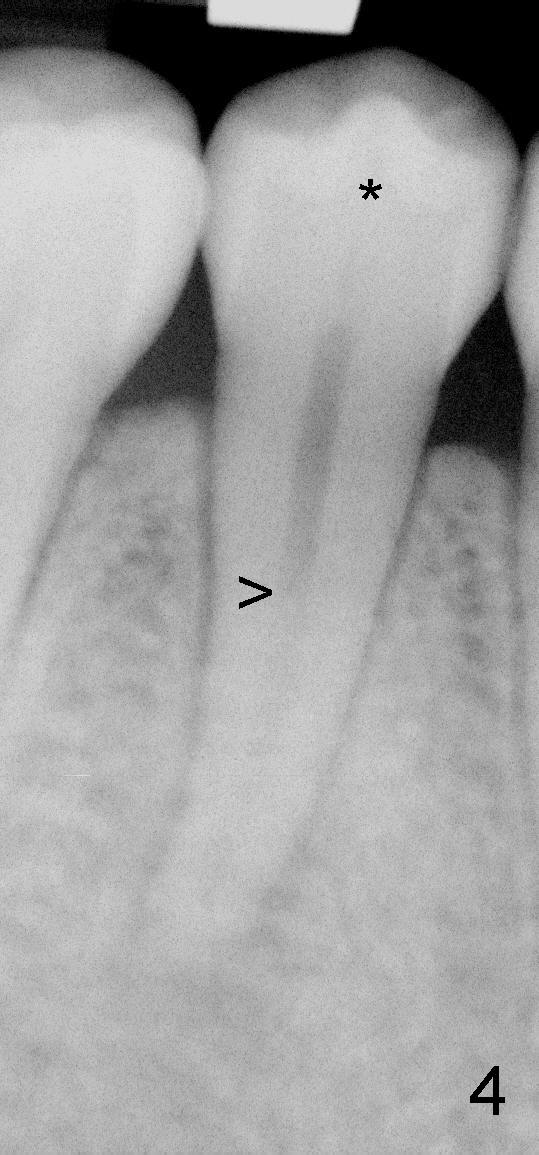

第二前磨牙根管也有突然变化(图四箭头,这么清晰似乎第一次遇见),所以这个牙齿有两个根管(颊侧,舌侧)。根尖阴影可能是因为中央牙尖断裂(*)造成的。